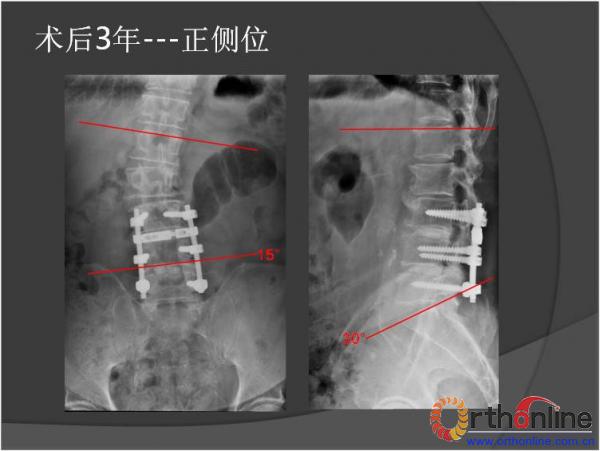

北京军区总医院骨科李放教授报告了一例腰椎管狭窄脊柱融合术后、退变侧凸加重并出现邻近节段退变病、而后进行翻修的病例。患者男性,64岁,2009年因腰椎管狭窄症行椎板减压,L3-4、L4-5PLIF手术,术后3年间疗效满意,后由轻度扭伤后再度出现腰痛及下肢疼痛,经检查后发现L2-3间盘退变、L1-2间盘突出并出现退变性腰椎侧凸,于2013年2月行翻修手术后痊愈。